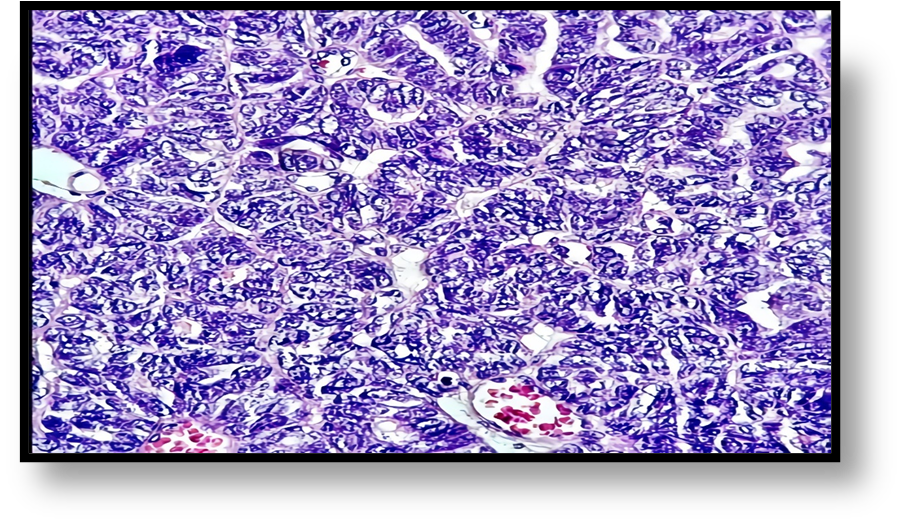

Diagnosed with a benign right adnexal tumor, a laparotomy was performed that revealed a 15x12 cm right ovarian tumor with a cystic component and a 14x5 cm right hydro salpinx with chocolate-like content through its wall (Figure 3). Total hysterectomy plus bilateral salpingo-oophorectomy was performed with a report of ovarian cystadenoma and endometroid adenocarcinoma of the right Fallopian tube. It showed dilation and the section revealed a nodular lesion, in its distal third, with a papillomatous appearance, white-yellowish, of a soft, sessile consistency, with endophytic growth of 2x1.5x.2cm (Figures 4, 5). The microscopic study showed a neoplasm of epithelial origin with a glandular, cribriform, papillary and even solid growth pattern that did not infiltrate the underlying capsule, (Figures 6, 7, 8).

(Figures 9, 10) show cellular details of the Endometrioid Adenocarcinoma: Papillary formations and less differentiated solid areas. Cells are medium to small, with scant cytoplasm, moderate atypia, granular chromatin, irregular nuclei, nuclear moulding and few mitotic figures. The uterus reported some fibroids from 1.5 to 3 cm and the contralateral annex without alterations.

Figure 9: Show cellular details of the Endometrioid Adenocarcinoma: Papillary formations and less differentiated solid areas. Cells are medium to small, with scant cytoplasm, moderate atypia, granular chromatin, irregular nuclei, nuclear moulding and few mitotic figures.

Figure 10: Microphotography 400x. Cellular detail of Endometrioid Adenocarcinoma. Papillary formations. Better differentiated areas. Cells are medium to small, with scant cytoplasm, mild atypia, granular chromatin, more regular nuclei, scant nuclear molding, few mitosis figures.

The microscopic description of this neoplasm is characterized by showing an architecture that varies between glandular, papillary and solid formation with cells showing endometrioid differentiation [7, 10, 13]. In our case, the microscopic study showed a nodular endometrioid carcinoma with papillary formations, a solid, cribriform pattern and with few mitoses, characteristics that correspond to endometrial endometrioid carcinoma [2.8].